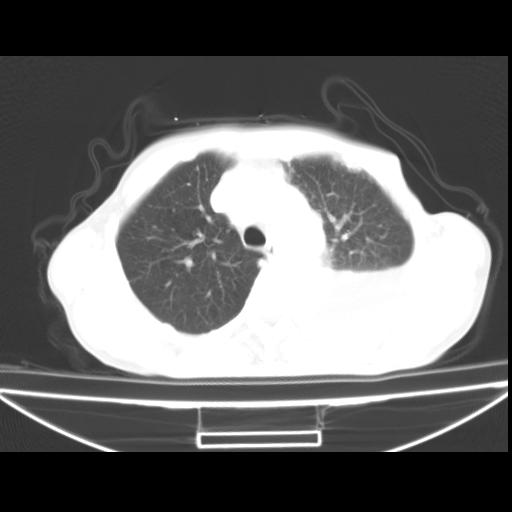

以下是引用随光逐影在2010-3-24 19:15:00的发言:[br]结合病史,考虑双肺及纵隔淋巴结多发转移、左侧胸膜转移并左侧大量胸水,左下肺膨胀不全。

以下是引用zxl51642在2010-3-24 18:49:00的发言:[br]结合乳腺癌术后病史,考虑双肺及纵隔淋巴结多发转移、左侧胸膜转移并左侧大量胸水、左下肺膨胀不全。